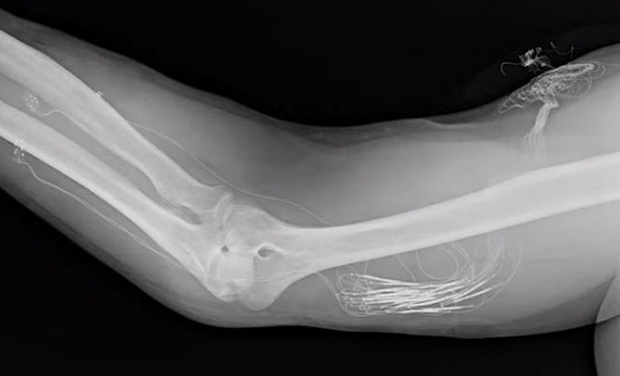

Тактильный интерфейс для искусственной конечности пытались создать и раньше. Например, в рамках программы DARPA HAPTIX идёт разработка нейроинтерфейса для передачи тактильных сигналов от протеза в нервную систему. На рентгеновском снимке внизу видны электроды, хирургически имплантированные в предплечье и подключенные проводами к внешнему компьютеру. В идеале, сенсорные сигналы от протеза поступают через тактильный интерфейс в периферийную нервную систему, оттуда — в спинной

Электроды, хирургически имплантированные в предплечье и подключенные проводами к внешнему компьютеру